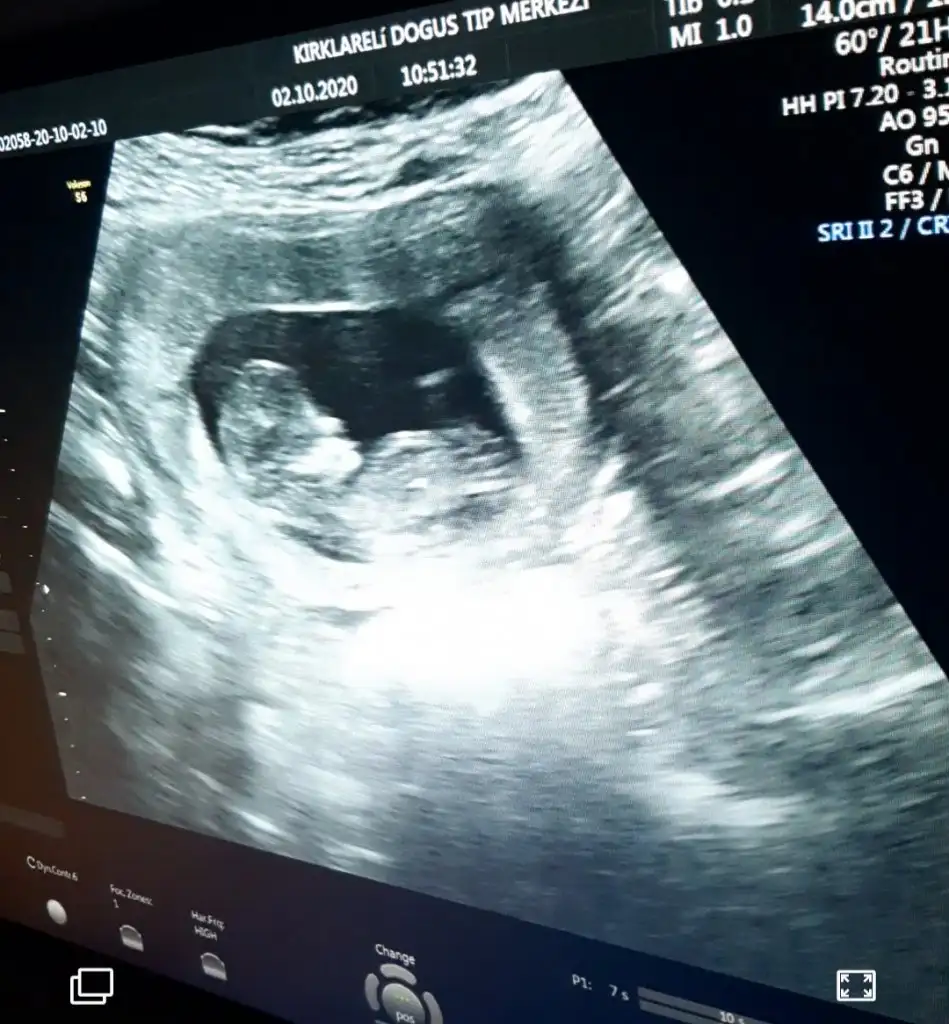

Kızlar selam devlete gittim ama rezalet resmen sağlam giren hasta çıkar o dereceydi bakmadı bile bir kafasına baktı okdr 14hafta erken belli olmaz dedi ben tabi duramadım hemen özelden başka doktordan randevu aldım oda 14de gelince niye ara dönemde geldin cinsiyet için dimi kendi doktorunuzu bekleseniz diye fırçaladımı

neyse baktı etti dedi kız gibi ama net göremiyorum yüzüstü duruyor dedi ama net kız diyemem dedi bekle 16yı dedi sağolun dedim

bekleyin kızlar gibilerle kafa daha çok karışıyor bide siz bakin bakim fikriniz ney☺